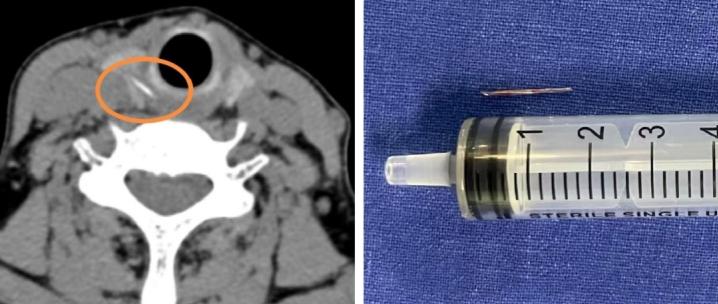

影像結果證實,在劉阿姨右側甲狀腺位置,發現了一條索狀的高密度異物影,極有可能是魚刺穿透食道壁,扎進了甲狀腺。

手術中,醫生小心翼翼地探入頸部,精細地分離組織,完好地保護了甲狀腺、甲狀旁腺以及喉返神經,最終成功從右側甲狀腺中,取出了一枚長約1.5釐米的魚刺。